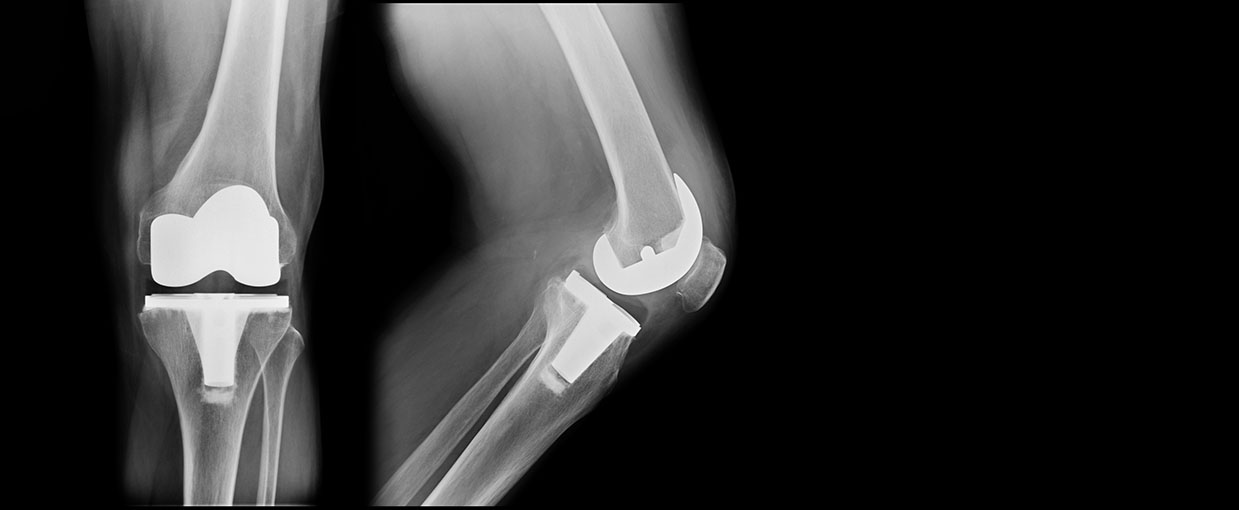

Bilateral Total Knee Replacement Stock Image C003/4806 Science